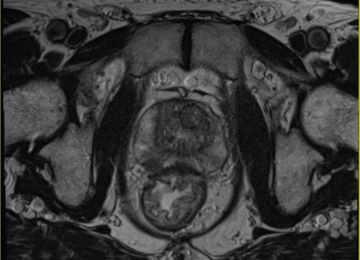

MRT Prostata

Hier finden Sie wichtige Hinweise zu dieser Untersuchungsmethode (mp-MRT, MRT-Prostatographie).